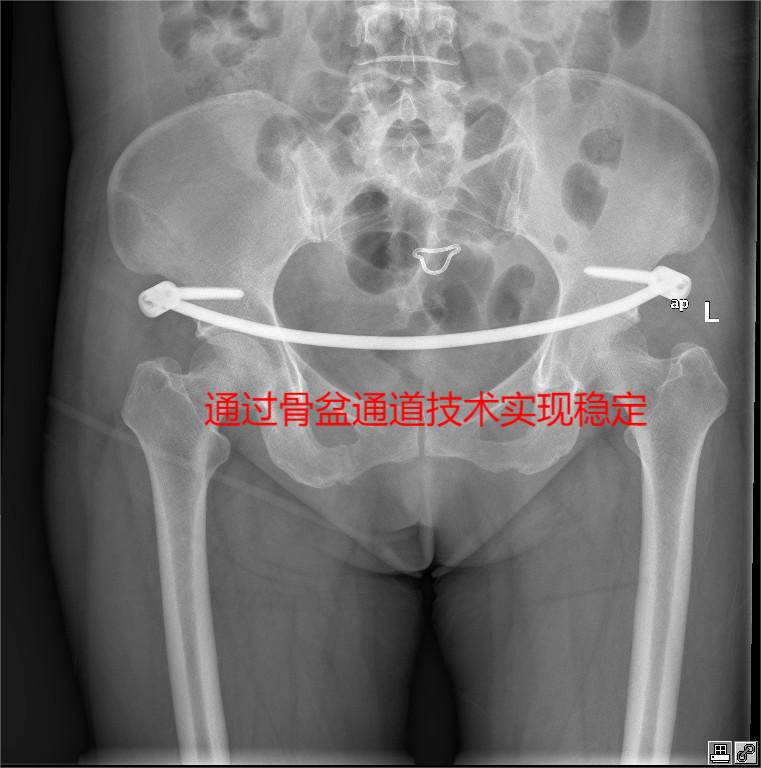

术后图像:

入院后行骨盆骨折闭合复位,infix内固定+LC2经皮空心螺钉内固定术。术后恢复良好。

面对复杂病情,我院创伤中心迅速启动多学科协作(MDT)机制,骨科、麻醉科、ICU专家共同会诊,制定“精准微创、损伤控制”的治疗方案。针对不同患者的骨折类型,团队量身定制手术路径:对骨折移位相对集中的患者,采用骨盆经皮通道技术,通过2cm左右的微小切口,在术中透视实时引导下将螺钉精准置入骨折部位,无需广泛剥离软组织,最大限度保留骨盆周围生理结构完整性;对涉及前后环联合损伤的复杂病例,则应用改良腹直肌旁入路,经肌间隙与腹膜外间隙进入术区,避免切断肌肉与神经牵拉,在清晰视野下完成骨折复位固定,兼具微创性与稳定性优势。

与常规髂腹股沟入路切口对比(上图),我院采用经皮通道螺钉技术(下图)微创效果显著。